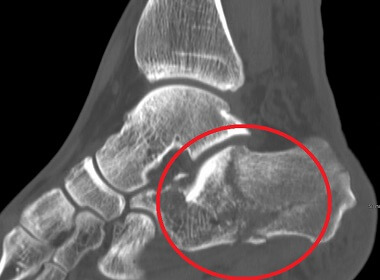

One of the most potentially serious heel pain causes is a fracture or break in the heel bone.

Heel fractures may be caused by:

Calcaneal fractures typically result in severe heel pain which can make it difficult to take any weight through the foot and are usually associated with significant foot swelling.

You can find out more about fractured heel pain causes, symptoms and treatment options in the Stress Fractures section.